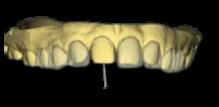

(FIGURA 1)

En la (figura 1) se observa el escaneado de los modelos de yeso que se le tomaron al paciente para diseñar las carillas dentales